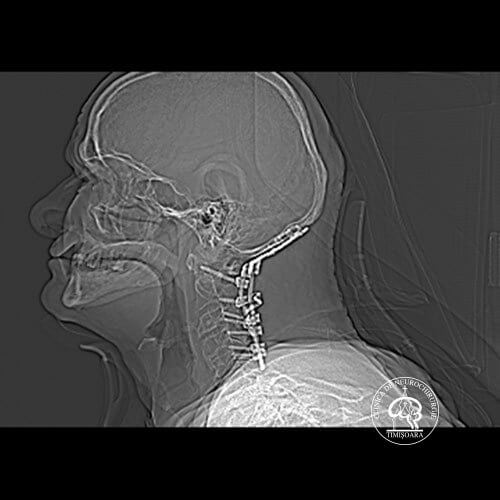

Patologia coloanei vertebrale